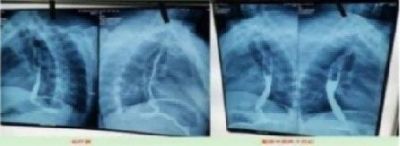

导语:近日,一名患者在中国专家陈教授的治疗下,成功将肺癌肿块体积由初诊时的8.5 CM x 3.9 CM,减小至3.6 cm x 2.6 CM。这一惊人效果,被誉为全球性的医学奇迹。

Recently, a patient, under the treatment of Chinese expert Professor Chen, successfully reduced the volume of lung cancer mass from 8.5 CM x 3.9 CM at the initial diagnosis to 3.6 cm x 2.6 CM. This amazing effect has been hailed as a global medical miracle.

据了解,陈教授所采用的是一种以中药为基础的治疗方法(中药疗法)。经过近一个月的治疗,奇迹般的见证了患者病情的好转——肿瘤体积迅速减小。在一般情况下,如没有有效的治疗手段进行干预,患者的肿瘤体积通常会随着时间的推移而持续增长。

Subject: It is understood that Professor Chen uses a treatment method based on traditional Chinese medicine (traditional Chinese medicine therapy). After nearly a month of treatment, the miracle witnessed the improvement of the patient's condition —— the tumor volume decreased rapidly. In general, without an effective treatment for intervention, a patient's tumor volume usually continues to grow over time.